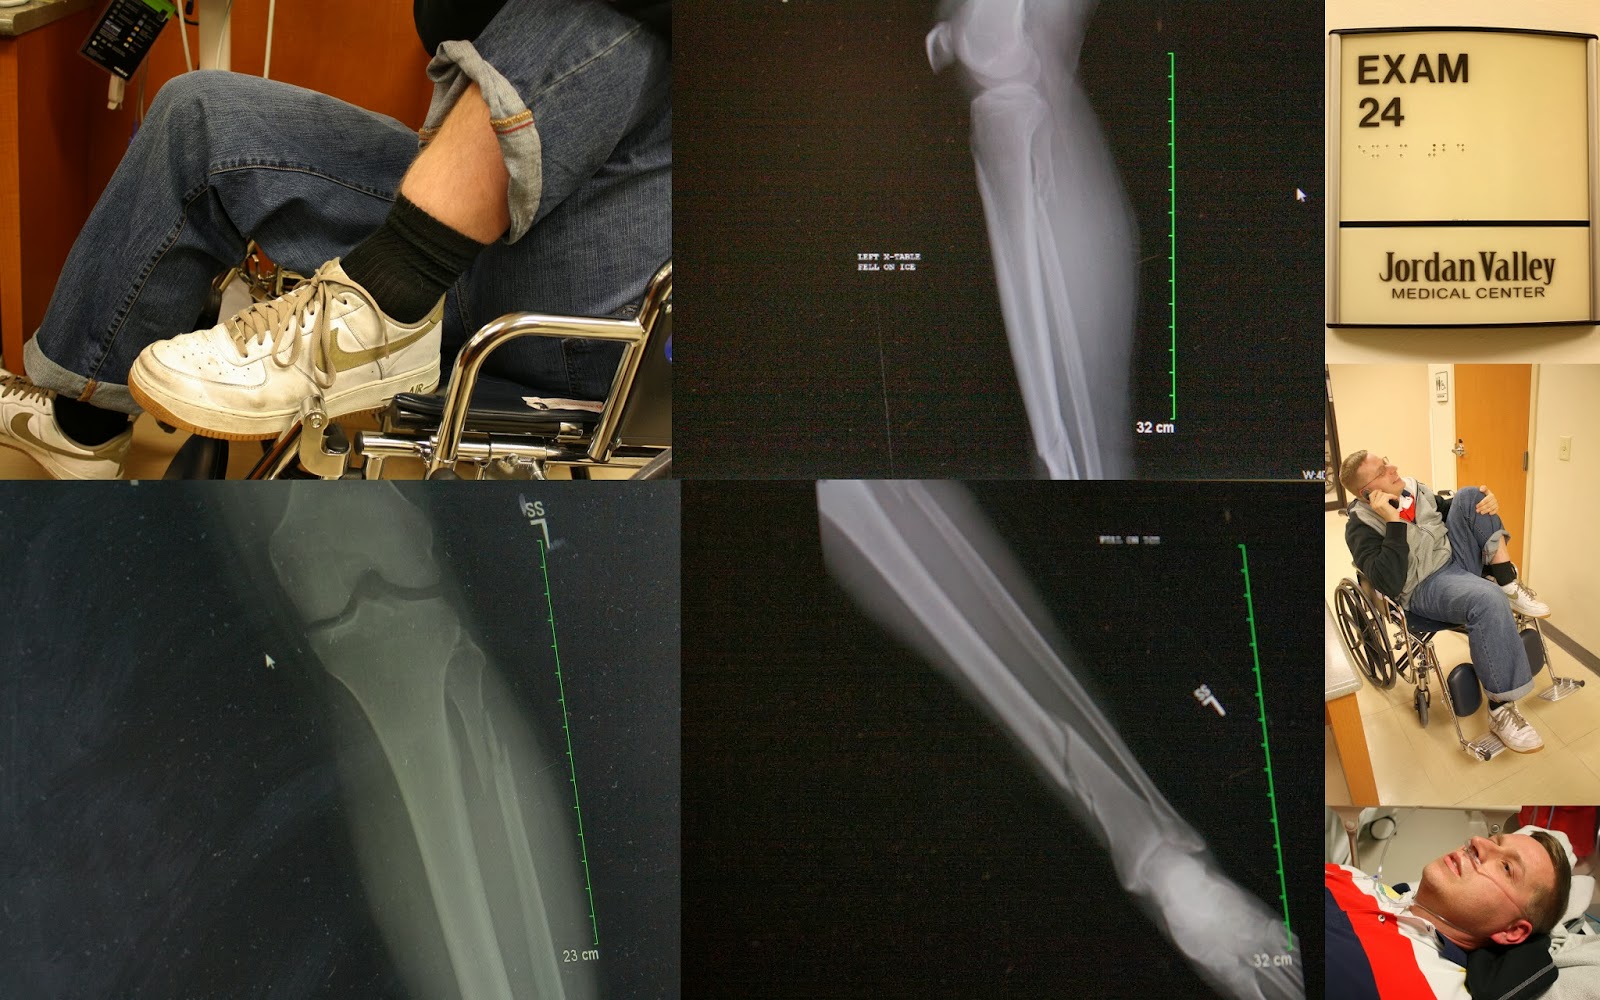

Paul {age 35}: Uh, he broke his leg in three places. Should I go on? Kind of ended our year with a bang. Okay, let me really think about it. I think he made some sort of personal record for movies he has seen in the theater by himself in a year. He bought a juke box, pool table, and a kiddie ride...which were all new machines to our business. He continued eating all the baked goods he desired, even after the stern talkin' to by the Doctor.

December 10th, 2013

We decided to go see Frozen as a family, and were on happy high as we drove home singing all the songs from the sound track. We came home to find fun Christmas boxes on our front porch. I start herding children inside, Paul goes to get the boxes. In the middle of taking shoes off, and starting the Papa Murphy's Pizza...I hear Paul scream from the front sidewalk.

He slipped on the ice, and was holding his leg. A neighbor ran to help, and Paul asked for an ambulance. I was the mean wife, and said suck it up and get him in the car {I have learned I need to work on my compassion!}.

My sweet neighbors {and friends} took our three littles, and we had a tearful drive to the emergency room. In my head I kept thinking it would be a few hours waiting around, and then we would be on our way. Paul made a few calls to his family, and I made one to Cathy. They all met us at the hospital to help calm us down. Paul got a Priesthood blessing, loads of drugs, a few x rays, and then the wait started. We decided after a couple of hours, I would take Uncle Jackie home to stay with the kids. While Uncle Shane stayed with Paul.

I wasn't gone for very long, but I wasn't expecting to come back to the ER to find the room empty where Paul had been. After a few questions, I was told he had been admitted and moved to a room. I tried to not freak out, but I knew the news wasn't going to be good.

I got the news from Uncle Shane...3 breaks. One by his knee, one in his lower leg, and his ankle. Surgery. Days in the hospital. 12 week recovery.

I cried. Paul cried.

Our world had been turned upside down.